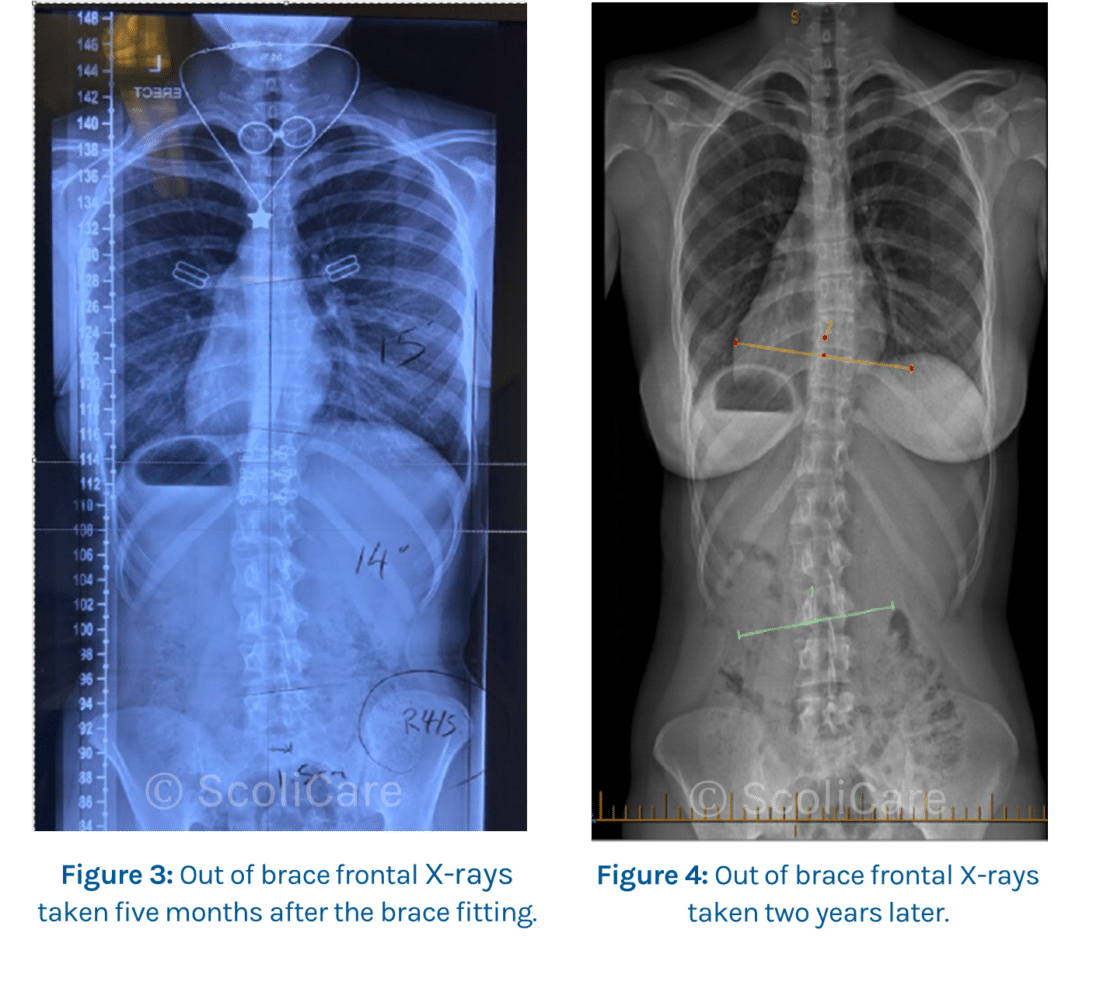

The patient’s spine responded favourably to the treatment with follow-up X-rays five months later showing that the initial thoracolumbar curve could be reduced from 34° down to 14° without the patient wearing the brace. The spine at this time was more balanced with a left thoracolumbar curve of 14° and a right thoracic curve of 15° (Figure 3).

At the patient’s follow-up two-years later, the curve out of brace had reduced to 16° in the thoracolumbar spine with no evident curve in the thoracic spine (Figure 4).